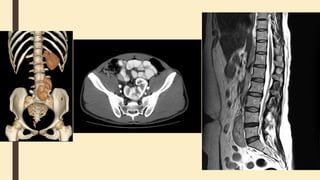

Computed tomography of kidneys,

ureters and bladder (CT KUB)

■ is a quick non-invasive technique for diagnosis of urolithiasis.